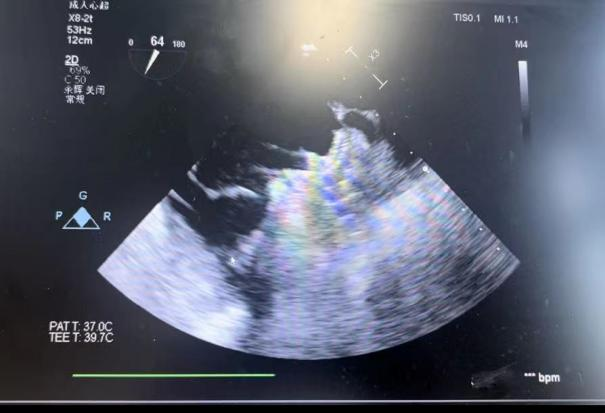

在食道超声引导下进行房间隔穿刺,由于心耳为反鸡翅型,穿刺位点需靠下靠前,潘教授先在90度双腔切面将定位靠下,再在45度主动脉短轴切面将定位靠前。穿刺成功后上导丝交换J9集团国际LAnavi™分段控弯导引系统送至心耳口部,经过A、B双弯的调整使得鞘管轴向与心耳同轴,获得理想封堵位置。然后推送钢缆释放出固定盘,锚定后退鞘释放出封堵盘。超声下观察贴合良好,无明显残余分流,牵拉测试稳定,即释放左心耳封堵器。释放后再次通过超声各个角度进行验证,封堵结果完美有效,整个过程一气呵成,手术取得了极大的成功。

牵拉测试稳定 完美有效封堵